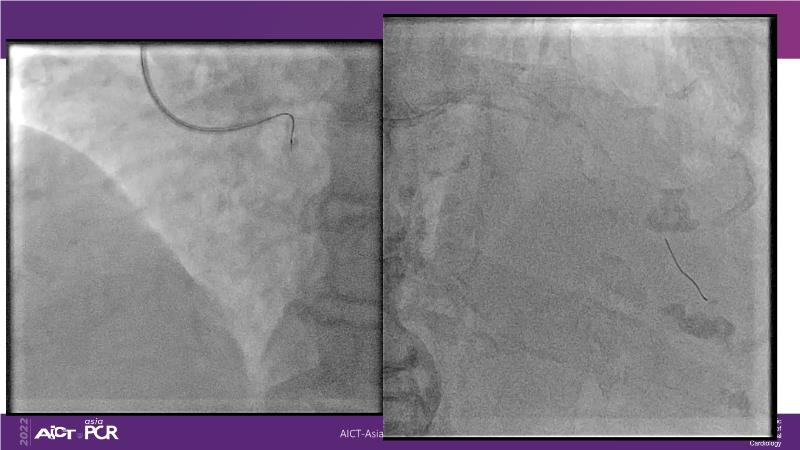

Cracking calcium: best practices to integrate intravascular lithotripsy into your calcium management algorithm

With this session, keep up to date on the evidence, trials and outcome data for intravascular lithotripsy in severely calcified lesions. Learn how to use this technique in real-world patients and understand its role in the treatment algorithm for severely calcified coronary lesions.